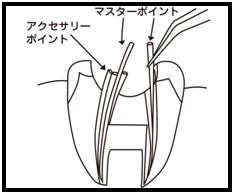

⑥ 前回詰めた綿花の状態を確認して、良い状態なら、「根管充填剤」(マスターポイント・アクセサリーポイント)というお薬を、余分な空間がないように根っこに詰めます。

⑥ 前回詰めた綿花の状態を確認して、良い状態なら、「根管充填剤」(マスターポイント・アクセサリーポイント)というお薬を、余分な空間がないように根っこに詰めます。 Q1.痛みはありますか?